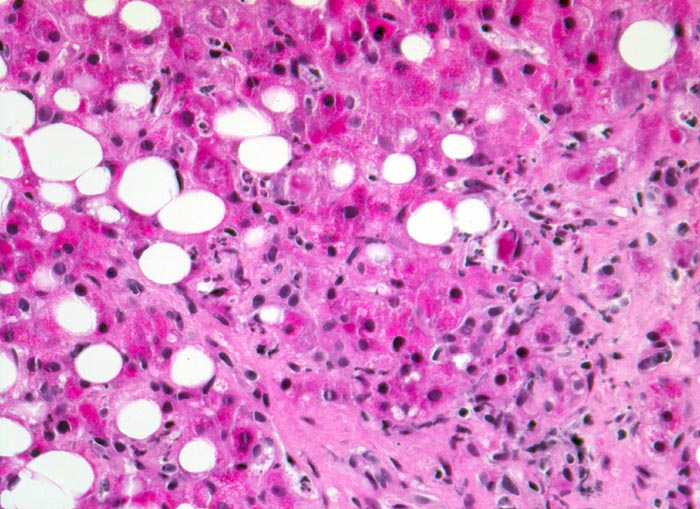

PathoPic ID 4948 - hochfloride chronische sklerosierende alkoholische Steatohepatitis

hochfloride chronische sklerosierende alkoholische Steatohepatitis

Leber

Grobtropfige Parenchymverfettung. Zahlreiche

neutrophile Granulozyten infiltrieren das Parenchym.

Alkoholabusus

Vergrösserung

200

Alter

49

männlich